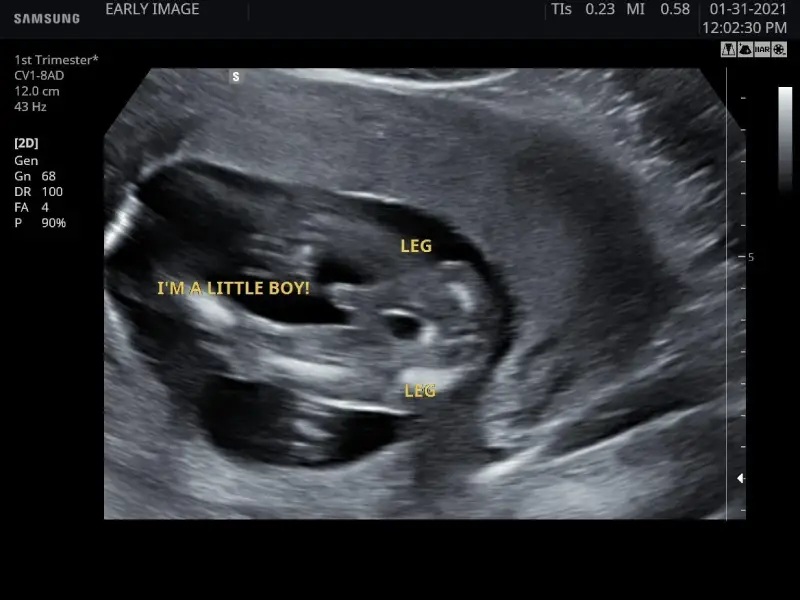

I’m a little boy

I’m a little boy (Live 5D)